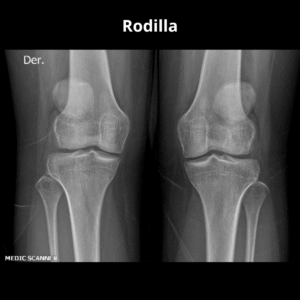

- Rodilla O Derecho O Izquierdo | O AP O LAT O OBL

- Rodilla O Der O Izq | O AP O LAT O OBL